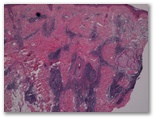

1582-R3Lesión nodular en cara externa del brazo.

1. Picadura

2. Linfoma B folicular

3. Nodulo escabiotico

4. Lupus eritematoso

5. Pseudolinfoma por vacunas (aluminio)